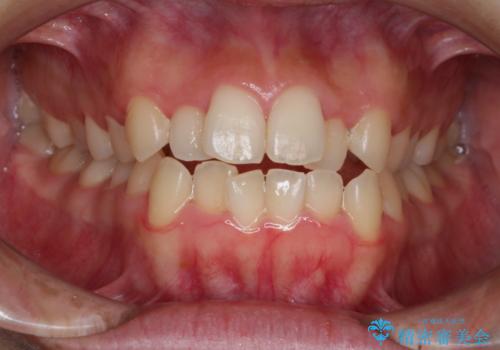

ディープバイトを改善するということは、当然奥歯の咬み合わせが相対的に高くなる or 前歯の咬み合わせが相対的に浅くなる、あるいはその両方によって達成されます。

マウスピースの使用による奥歯の咬み合わせの緩圧化は、これと相反する現象ですから、後戻りの観点からも一層注意深いフォローアップが必要かと思われます。

また、今回下顎はそれなりの叢生量がありましたが(ガタつきがけっこうあったが)、歯と歯の間を削ることなくコンピューターシュミレーションを組みました。

これにより、歯を削ることなくきれいに並べることはできたものの、下顎に対する下の前歯の角度がやや大きな仕上がりとなりました。